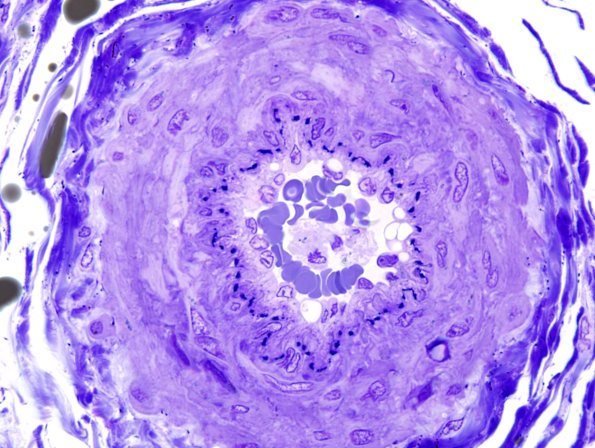

12A2 Artery, epineurial (Case 12) Plastic 1

A nice compact epineurial arteriole. (plastic section)